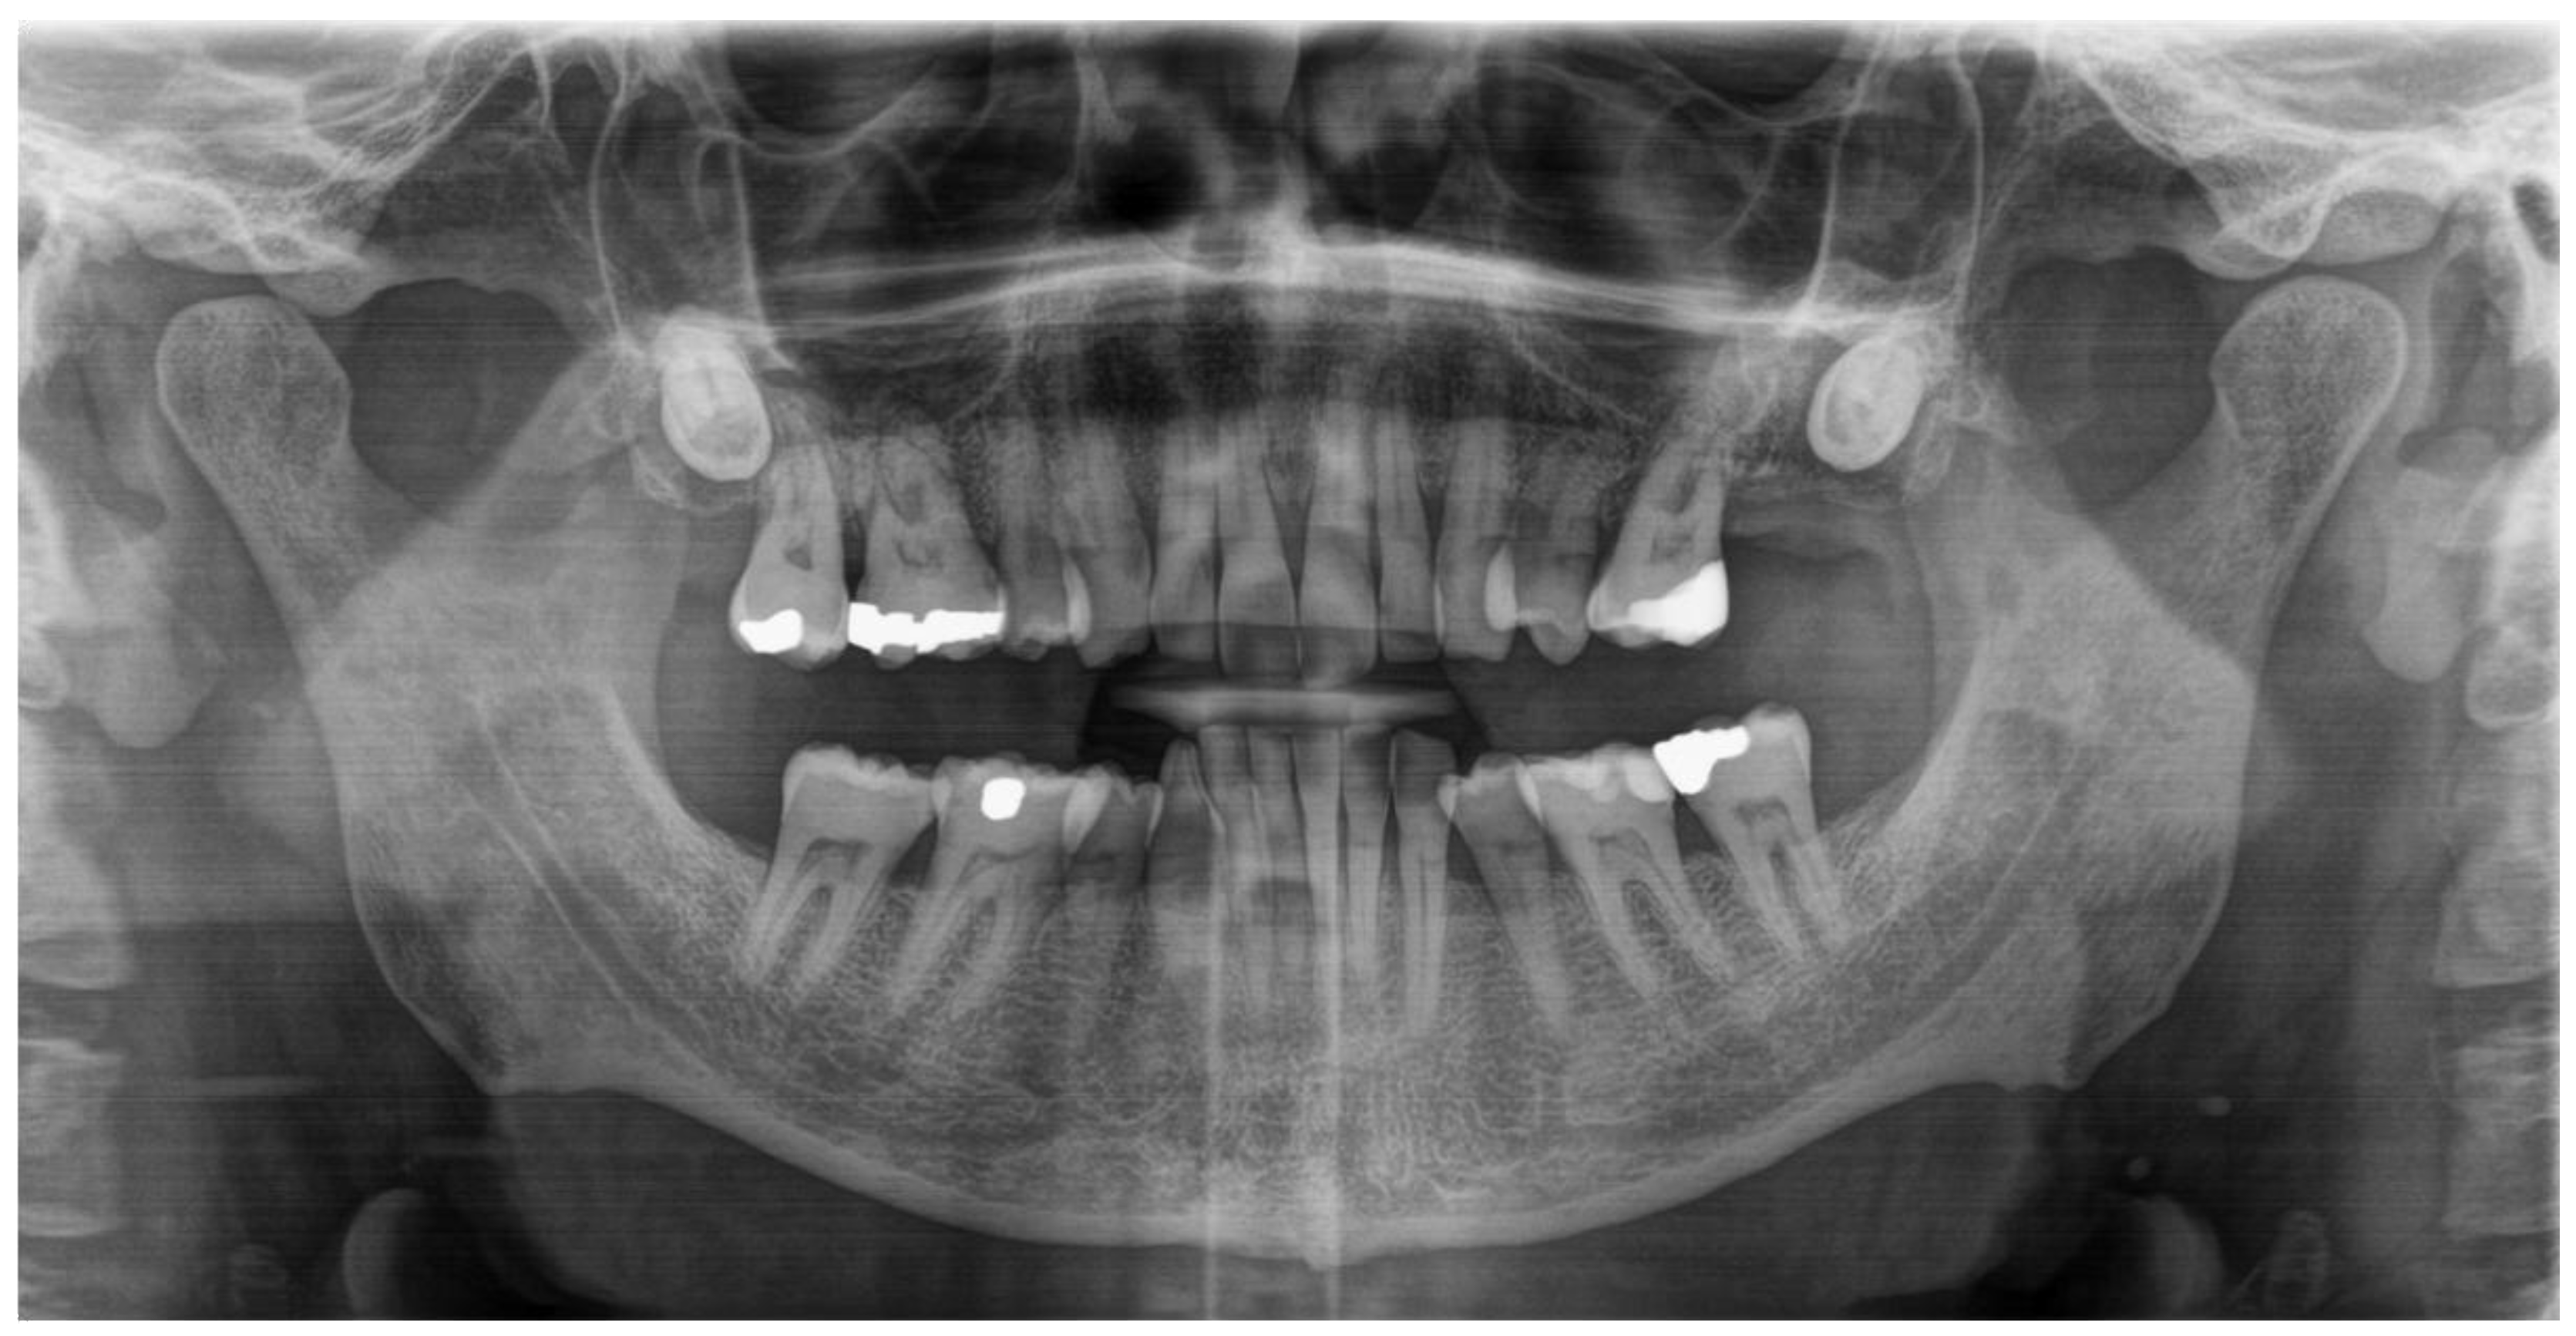

An orthopantomogram (OPG) was conducted as part of the X-ray-based diagnostic workup to evaluate the potential involvement of osseous structures within the jaws and surrounding anatomical regions that may have contributed to the lesion’s clinical presentation. The OPG revealed the absence of any underlying osseous pathologies or involvement of the mandible or maxilla, and did not reveal any pathological dental findings.